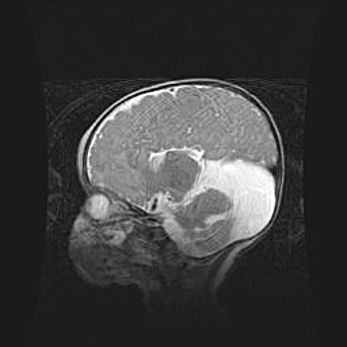

Множественные кисты обоих полушарий головного мозга, наибольшая из них в правой затылочной области. Ассиметричная атрофическая гидроцефалия.

Возраст: 7 месяцев

Вес: 5660 г

Пол: мужской

Окружность головы: 41,5 см

Срок гестации: 28-29 недель

Кисты головного мозга развиваются в результате многоочаговых некрозов вещества мозга и возникают вследствие перенесенной перинатальной инфекции, менингитов, энцефалитов, асфиксии, родовой травмы, расстройств мозгового кровообращения различного генеза. Образованию кист в веществе головного мозга плодов и новорожденных способствуют такие факторы, как высокое содержание в нем воды, недостаточная (или отсутствие) миелинизация и слабая астроглиальная реакция на повреждение.

Кисты могут сочетаться с гидроцефалией и другими поражениями головного мозга.